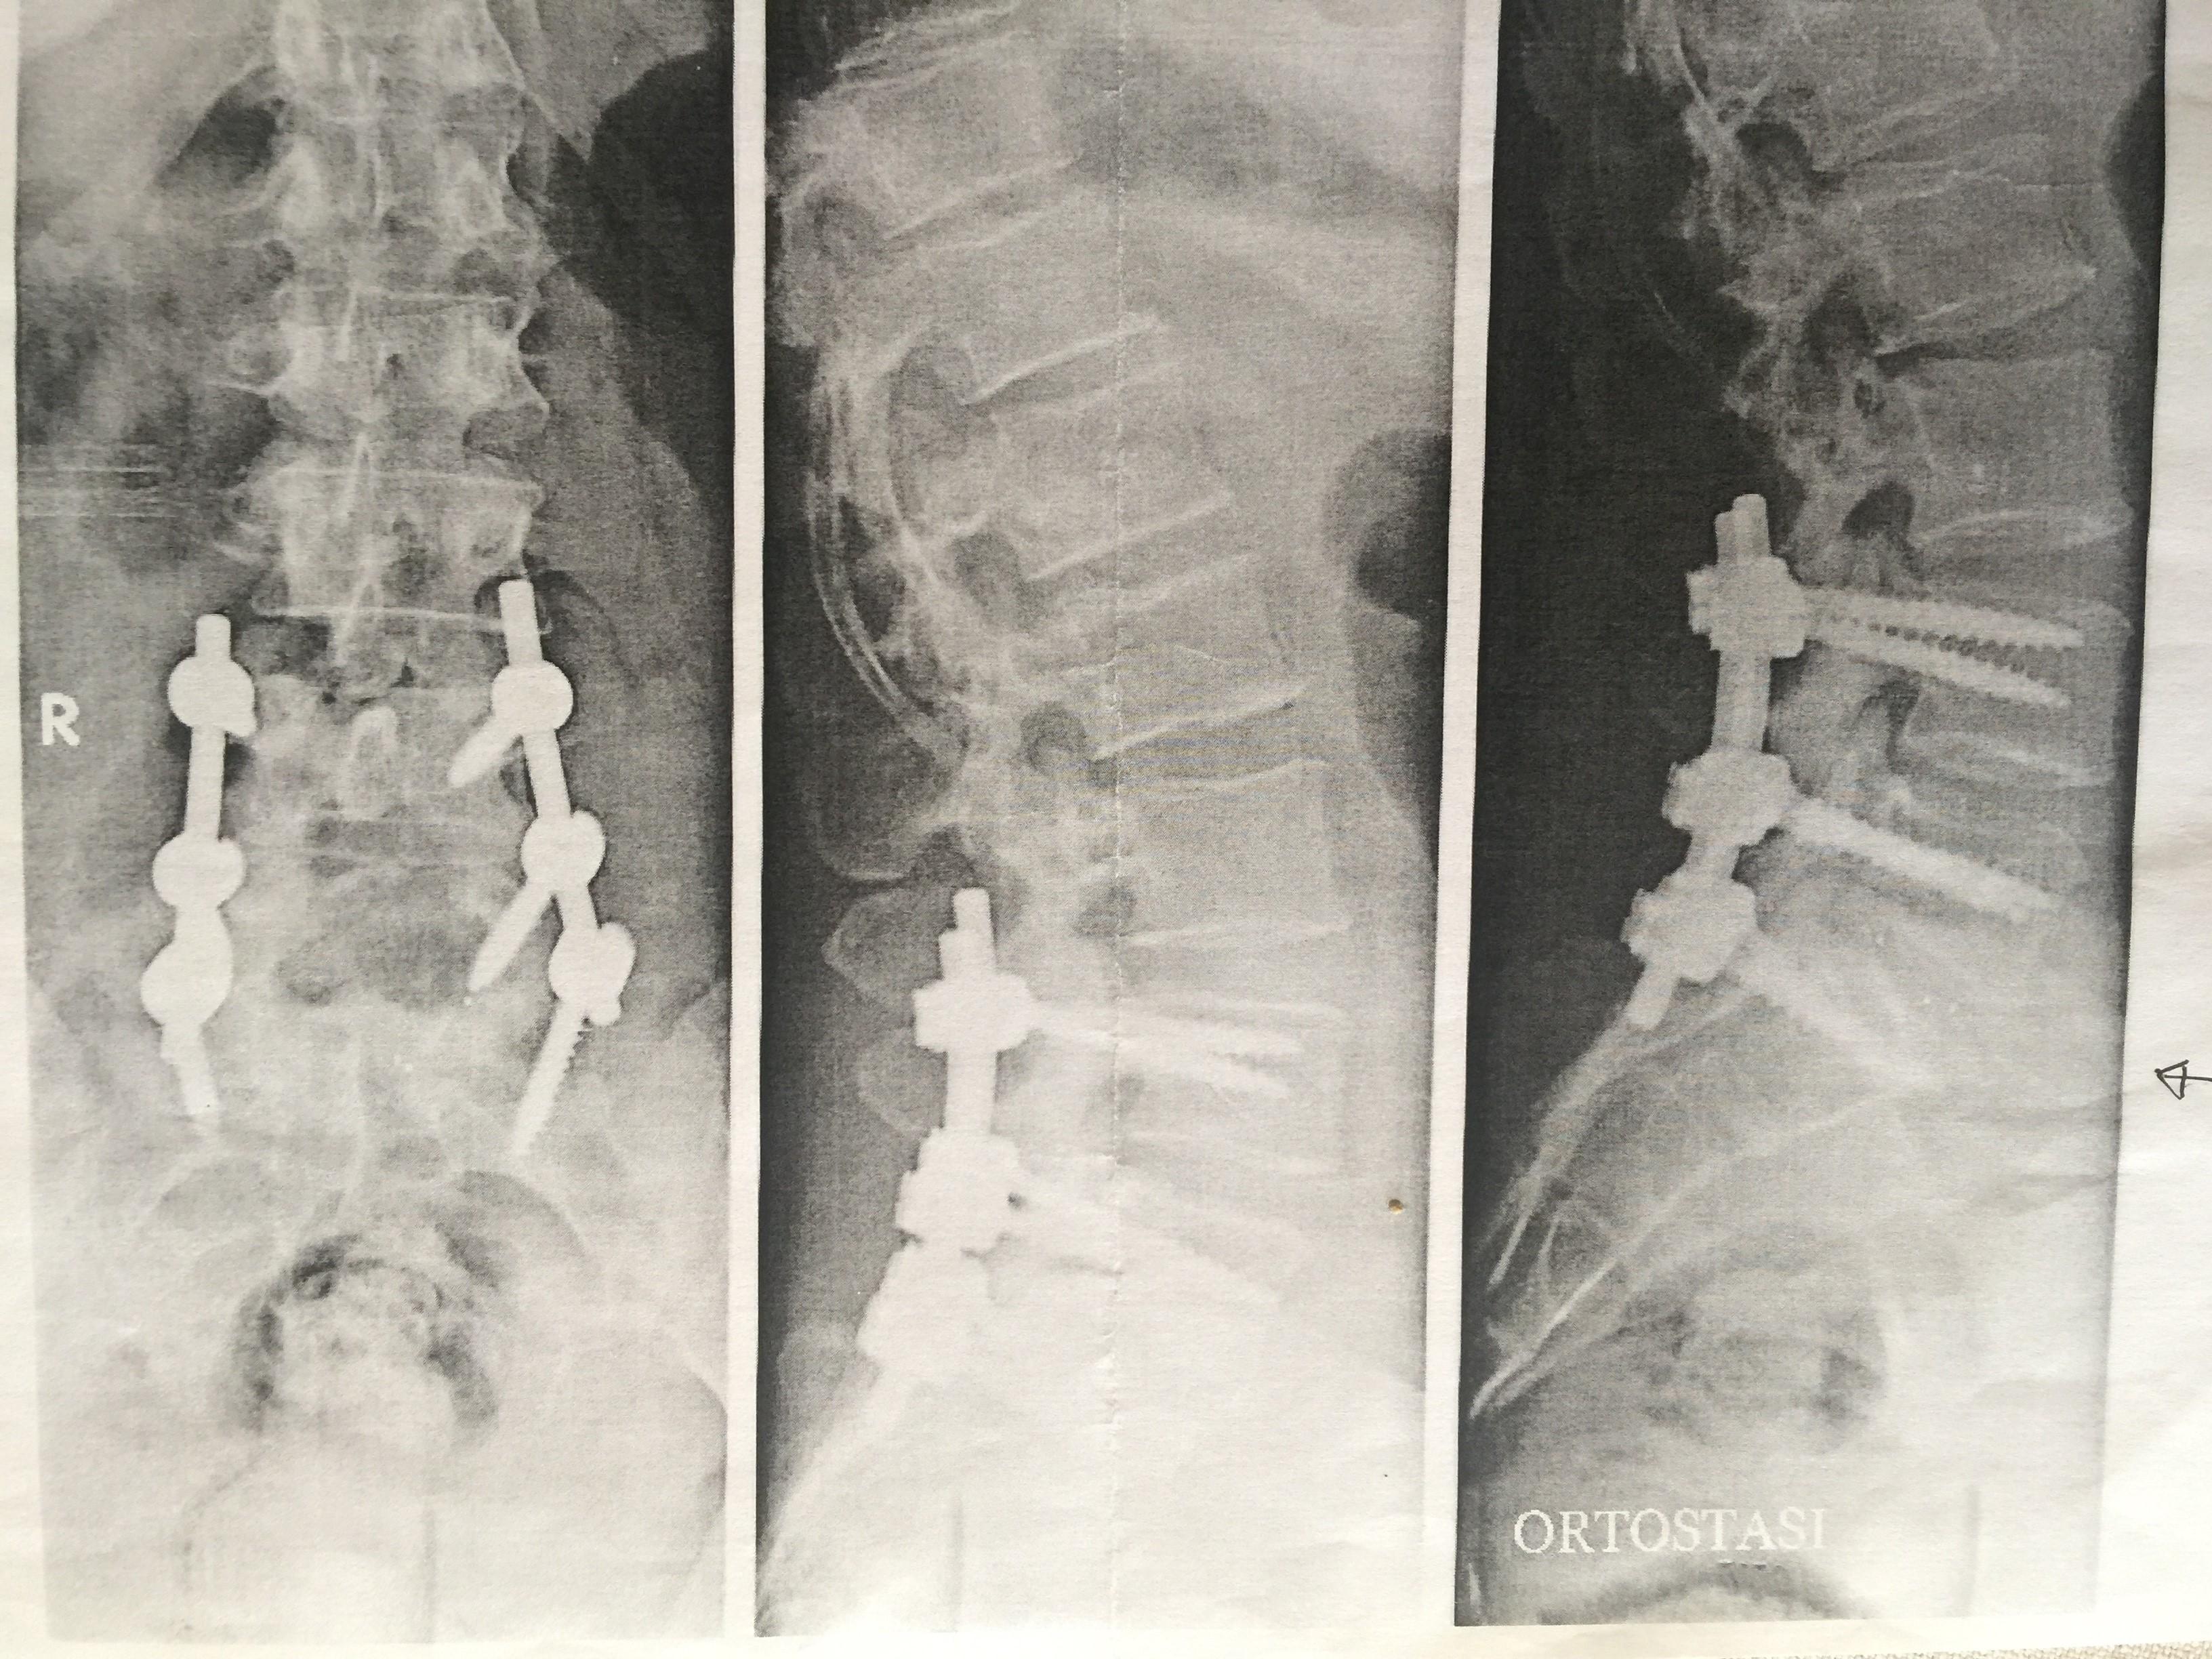

SASSARI. Dolori molto forti alla schiena, una risonanza magnetica con diagnosi di ernia discale, un intervento chirurgico che - almeno sulla carta - avrebbe dovuto risolvere il problema.

Ma proprio quell'operazione, eseguita all'Iccs (Istituto clinico Città di studi) di Milano, l'ex clinica Santa Rita, è stata l'inizio di un incubo: «La mia situazione attuale è drammatica - scrive la paziente, una donna sassarese di 44 anni, nella denuncia querela presentata in Procura - Riesco a malapena a camminare in poche occasioni portando obbligatoriamente un busto di sostegno. Convivo con gli oppiacei, unico farmaco che il mio medico curante mi somministra per attenuare il dolore».